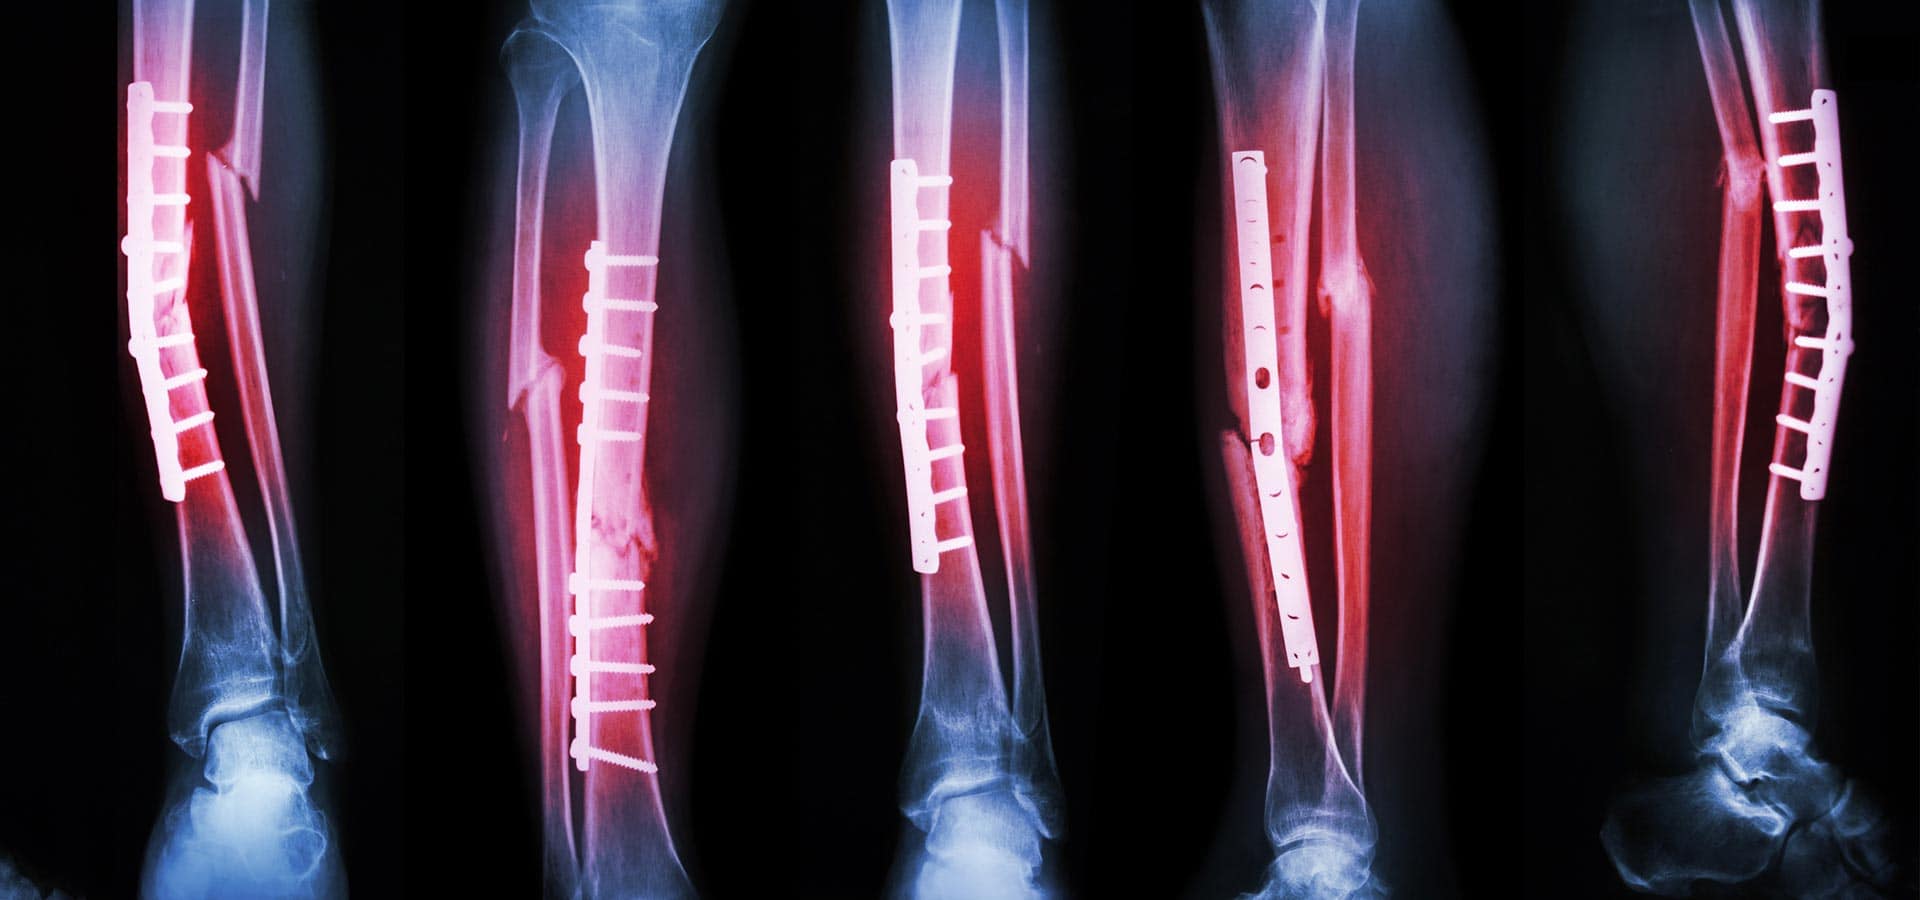

Для мене медицина — це безперервний процес навчання. Я отримав ґрунтовну фундаментальну освіту в Полтавському державному медичному університеті та пройшов інтернатуру з ортопедії і травматології. Проте я глибоко переконаний, що професіоналізм лікаря вимірюється його готовністю постійно вдосконалюватись. Саме тому я регулярно проходжу навчання та курси підвищення кваліфікації, опановую найсучасніші світові техніки.

- 2021р. – AO TRAUMA Course “Basic principles of fracture management” (базові принципи лікування переломів), м. Київ.